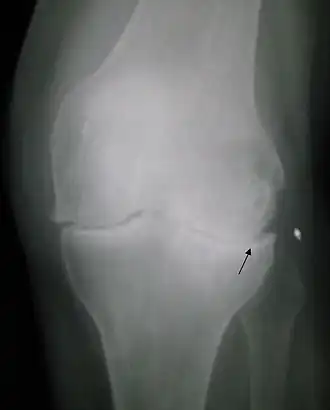

Radiologie

La radiographie standard, sans préparation, est suffisante au diagnostic de la maladie arthrosique.

Quatre signes radiologiques sont caractéristiques :

- le pincement de l'articulation par destruction du cartilage (diminution de l'épaisseur du cartilage) ;

- une condensation osseuse sous le cartilage ;

- la présence d'excroissances osseuses ou ostéophytes ;

- la présence de géodes (trous à l'emporte-pièce) dans l'os autour de l'articulation.

Il n'y a pas de parallélisme entre l'importance des signes radiographiques et les symptômes ressentis : une arthrose importante sur la radiographie peut rester asymptomatique. Inversement, une arthrose très douloureuse peut ne présenter que de modestes altérations radiologiques.